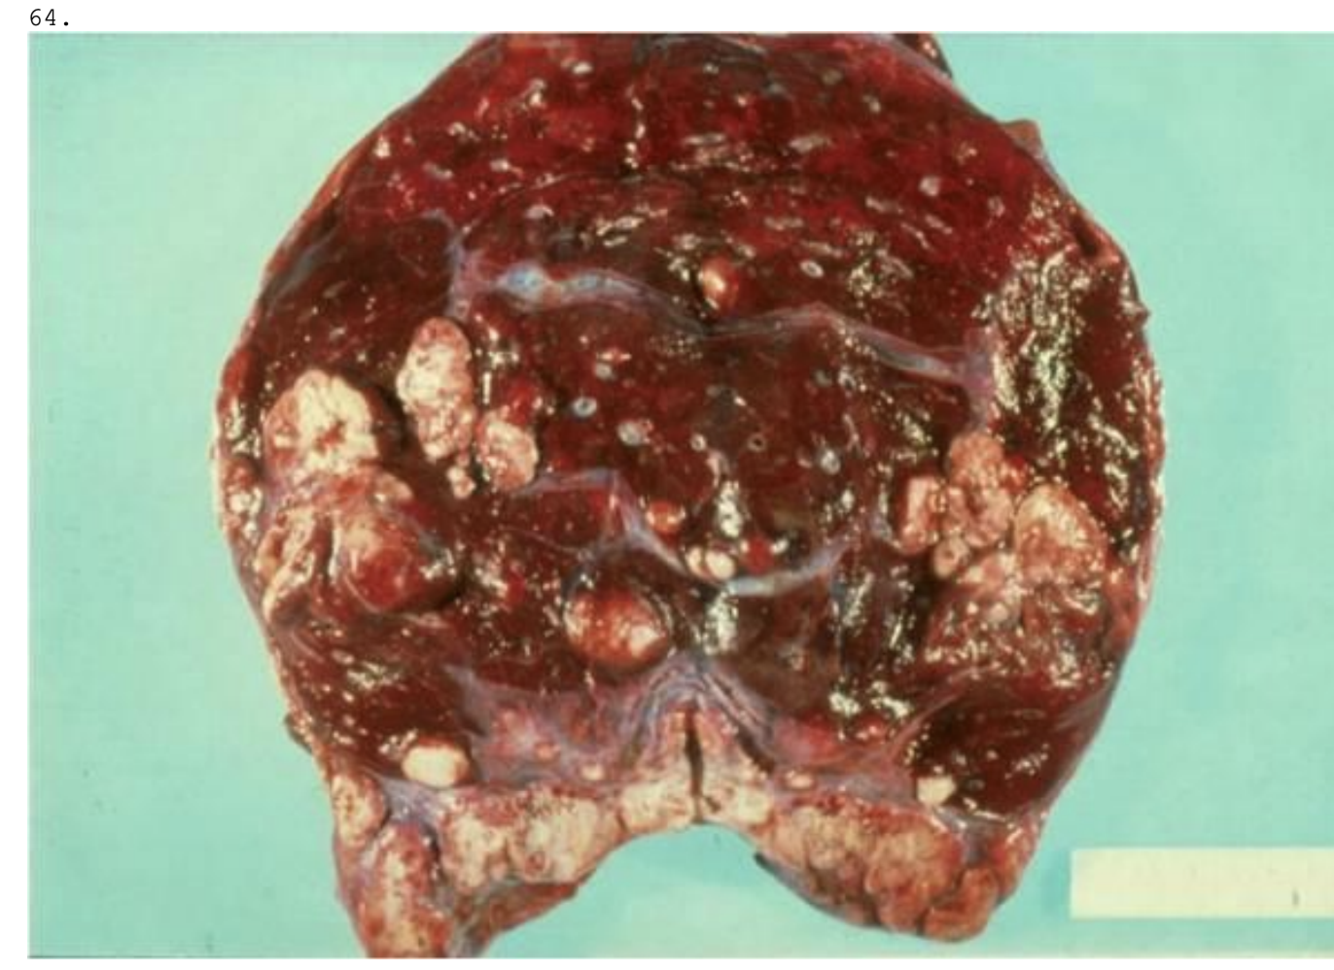

En 55-årig mand findes død i eget hjem. Ved obduktion ses forandringer i leveren som vist på billedet. Hvilket er følgende af udsagn er korrekt?

a. Der er tale om en atrofisk vækstforstyrrelse.

b. Tilstanden er ikke relateret til alkohol.

c. Makroskopisk beskrives leveren som forstørret og blød.

d. Tilstanden er irreversibel.

e. Mikroskopisk ses fibrøse strøg og regenererende hepatocytter.

*c. Makroskopisk beskrives leveren som forstørret og blød.